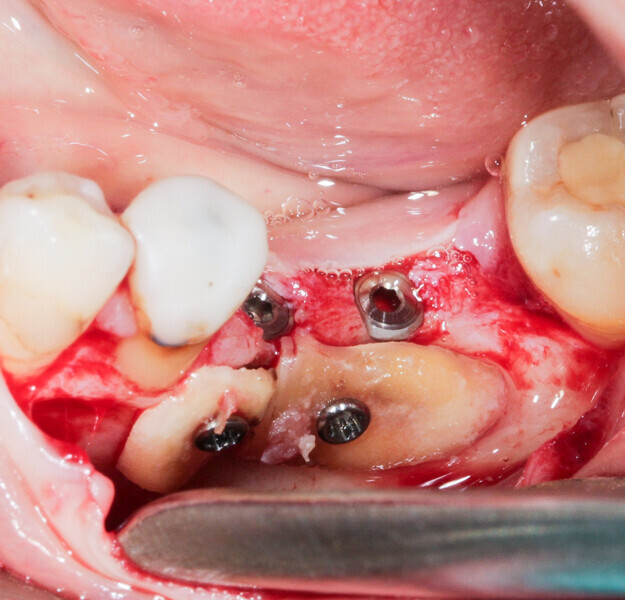

We had three alternative courses of action: a bone block graft from the mandibular ramus,2 a segmental osteotomy4 or a radicular graft, knowing that tooth #46 could not be saved. We chose the third option because it allowed for simultaneous implant placement and bone reconstruction. A large flap was elevated to assess the gap in the bone and in anticipation of closing the flap on an augmented ridge. Two implants were placed as normal despite the low residual bone thickness in the vestibular area of the planned positions for the implants (Fig. 5). The roots of tooth #46 were extracted atraumatically (root separation, use of piezo-surgery, etc.) and were then prepared as described. The roots were shaped to fit the defect and fixated at the insertion site using osteosynthesis screws (Fig. 6).3 The flap was mobilised and stretched to achieve edge-to-edge closure without tension, and a 4/0 rapidly resorbed braided thread was used for the sutures (Fig. 7). Four months after the bone augmentation and implant placement, healing abutments were connected to the implants and the osteosynthesis screws removed (Figs. 8 & 9). During the operation, time was taken to perform a visual check that ankylosis of the radicular grafts had been successful and that these were sound. Finally, a CBCT assessment was performed. The prosthesis was fitted by our colleague a few weeks later, once the soft tissue had healed.